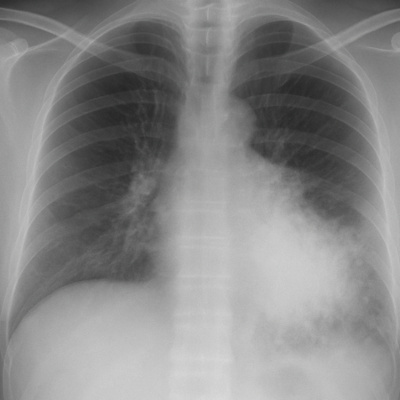

Learn how to diagnose and manage aspiration pneumonia in the ED with a twist. There's a board test answer and a "real life" answer for this one…Let's talk risk factors, key imaging findings, antibiotic choices, and when to worry.